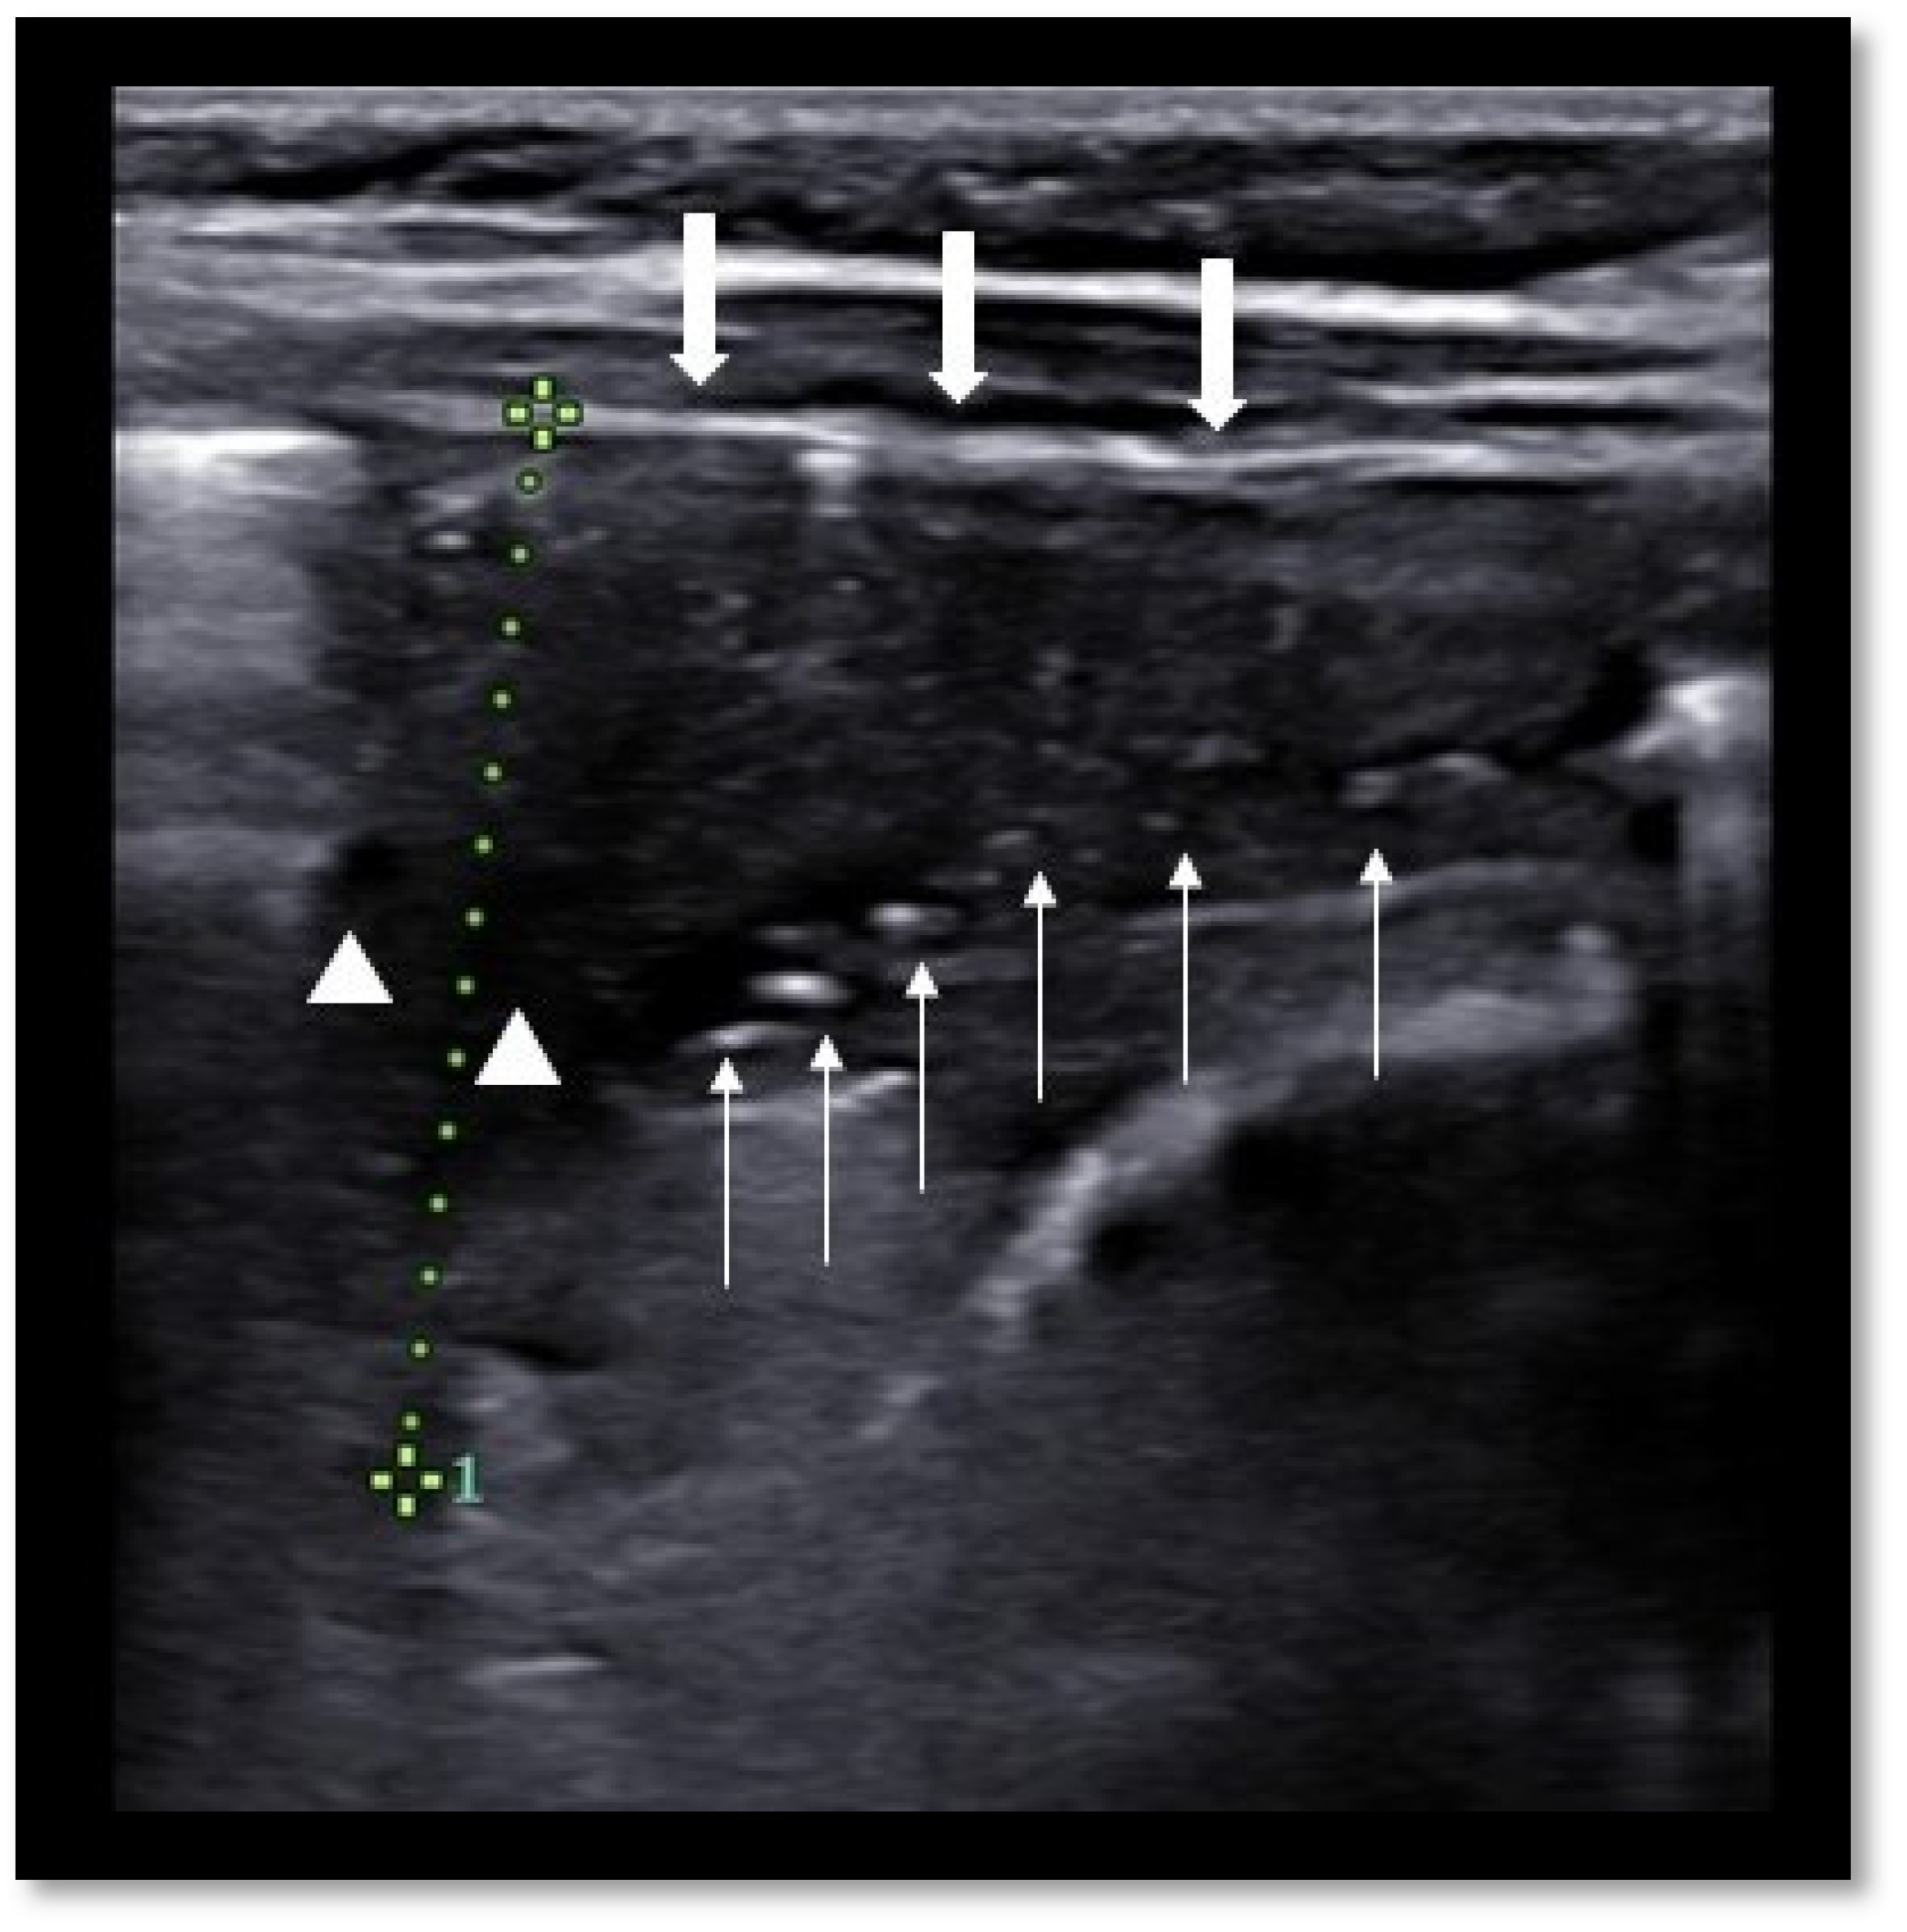

- Musolino, A.M.; Tomà, P.; Supino, M.C.; Scialanga, B.; Mesturino, A.; Scateni, S.; Battaglia, M.; Pirozzi, N.; Bock, C.; Buonsenso, D. Lung ultrasound features of children with complicated and noncomplicated community acquired pneumonia: A prospective study. Pediatr. Pulmonol. 2019, 54, 1479–1486. [Google Scholar] [CrossRef] [PubMed]

- Deganello, A.; Rafailidis, V.; Sellars, M.E.; Ntoulia, A.; Kalogerakou, K.; Ruiz, G.; Cosgrove, D.O.; Sidhu, P.S. Intravenous and Intracavitary Use of Contrast-Enhanced Ultrasound in the Evaluation and Management of Complicated Pediatric Pneumonia. J. Ultrasound Med. 2017, 36, 1943–1954. [Google Scholar] [CrossRef] [PubMed]